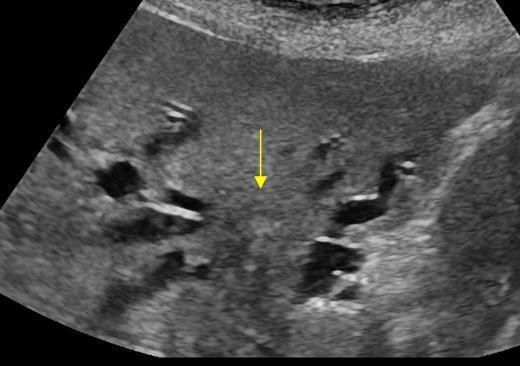

Caroli's Disease

congenital cystic dilatation of the intrahepatic biliary tree